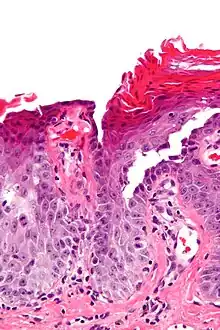

| Micrograph of transient acantholytic dermatosis, showing subcorneal separation and acantholysis. H&E stain. | |

Grover's disease (GD) is a polymorphic, pruritic, papulovesicular dermatosis characterized histologically by acantholysis[2]: 529 with or without dyskeratosis.[3] Once confirmed, most cases of Grover's disease last six to twelve months, which is why it was originally called "transient". However it may last much longer. Nevertheless, it is not to be confused with relapsing linear acantholytic dermatosis.